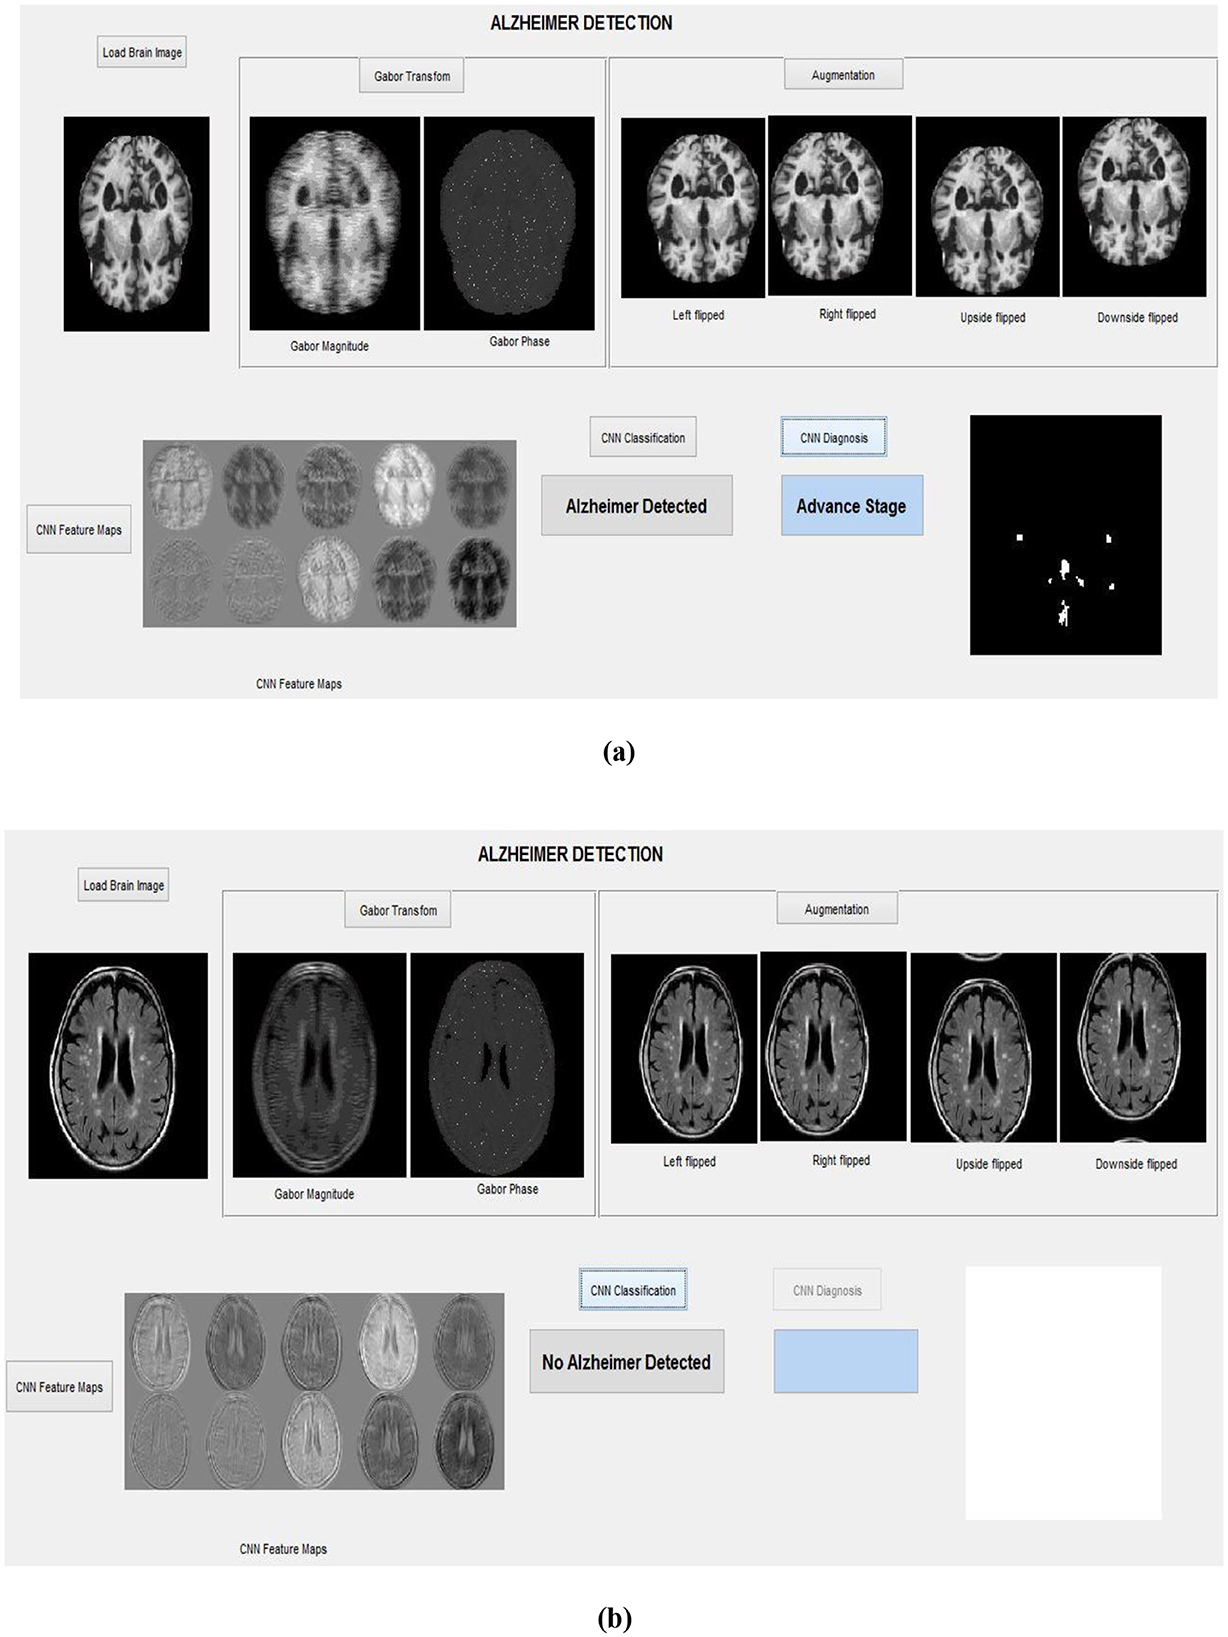

These segmented AP regions in the classified AD image are input into the RECNN classification algorithm for further analysis. Specifically, AP pixels from mild AD images and AP pixels from advanced AD images are trained separately by the RECNN algorithm to produce individual training patterns (ITPs). During testing, the AP regions in the classified AD image are processed by the RECNN algorithm against the ITPs, producing an output classified as either mild or advanced AD. Figures 8a, b present the simulation results from the testing phase, illustrating detection and classification outcomes for both AD and non-AD images. The results from each module are visualized through a graphical user interface.

Figure 8. Simulation results with the graphical interface: (a) Detection of an advanced-stage AD image, (b) Classification of a non-AD (healthy) brain image.